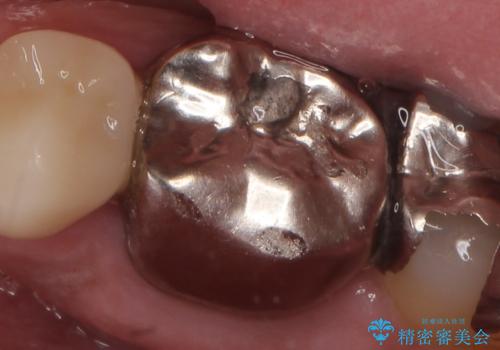

- 左下6番目の銀歯をオールセラミッククラウンにやり替えた症例です。

根管充填が不十分だったため再根管治療も行っております。